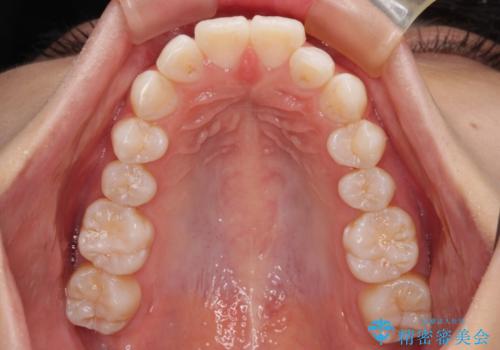

下顎はデコボコが気になっていたため、上下左右第一小臼歯4本を抜去して、ワイヤー装置にて口元の突出感を改善するよう矯正治療を行うこととしました。

下唇に前歯が当たって跡が残ってしまう状態でしたが、スッキリとした口元に仕上げることができました。